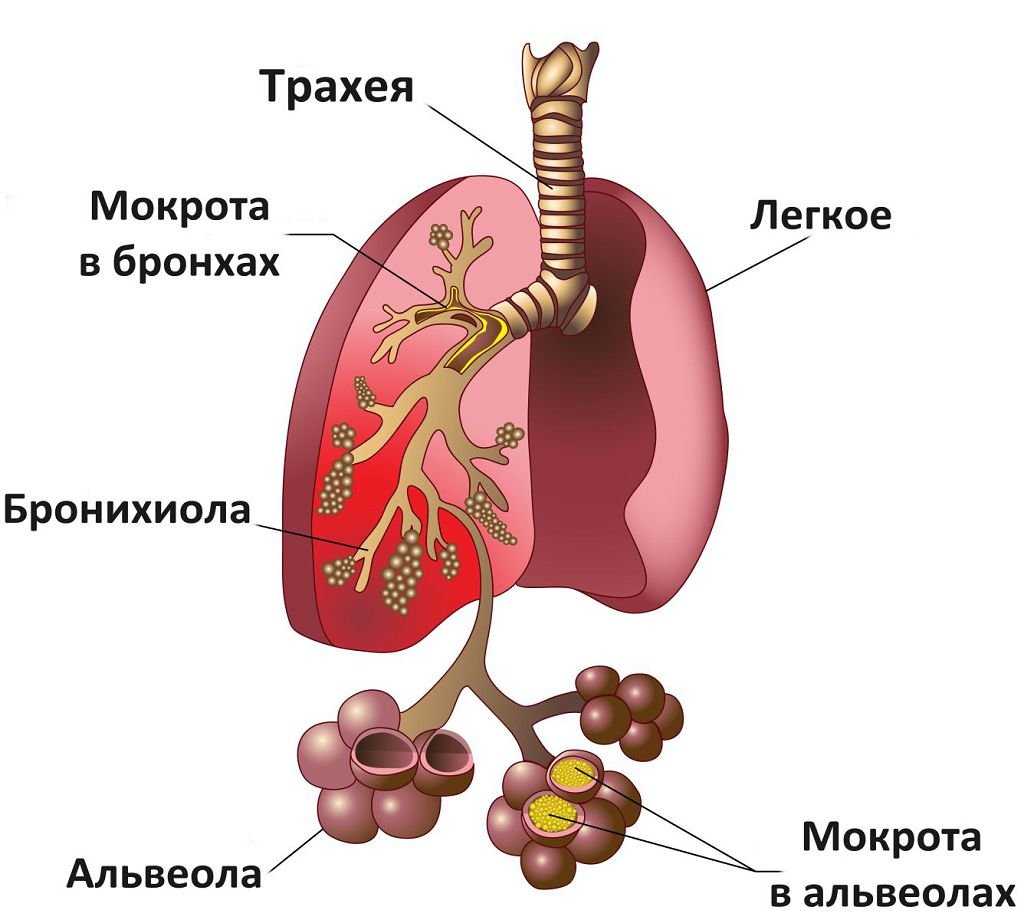

Пневмония может быть без кашля. Это бессимптомная пневмония. Появляется вследствие приема противокашлевых средств в большом количестве, из-за чего происходит подавление кашлевого рефлекса. Наблюдается накопление мокроты в легких, а это может ухудшить состояние.

Коронавирус переходит в нижние дыхательные пути, поражает альвеолы легких. Начинается воспаление. Это нарушает газообмен, приводит к одышке. Даже после восстановления от пневмонии у человека может длительное время оставаться дыхательная недостаточность.

Пневмония при коронавирусе – распространенное явление. Причем многие болезненные симптомы могут быть незаметными. Проблема усложнена большим количеством очагов воспаления в легочной ткани с блокировкой альвеол легких. В данном случае необходима своевременная медицинская помощь.

Чтобы точно убедиться в наличии пневмонии без температуры, поставить точный диагноз, специалист выслушивает жалобы пациента, осматривает грудную клетку, проверяет симметричность дыхания. Прослушивание легких позволяет выявить хрипы, а больные участки во время простукивания издают приглушенный звук.

Еще требуется анализ крови, мочи и мокроты. Рентген поможет выявить очаг воспаления в легких, его масштабы. Если есть подозрения на этот недуг, нужно сразу же обратиться к врачу. Самостоятельно поставить себе диагноз не получится. В больнице проводится полное обследование, что поможет точно определить вид заболевания.